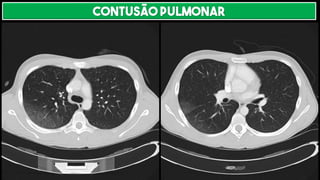

CONTUSÃO PULMONAR

Lesão do interstício ou alvéolo por TRAUMA ➔ REDUÇÃO DA TRANSPARÊNCIA DO PARÊNQUIMA

PULMONAR

TC

Lembra consolidação periférica

Pode ter aspecto em crescente

Não segue distribuição lobar

Proximidade do local do trauma

Distribuição não segmentar